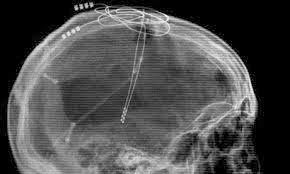

ripe for the picking, was at a working-group the other day for a presentation to some infosci/computing folks by a woman working on “non-intrusive” computer/brain interfaces and minutes after the touchy feely help the disabled bit came the military apps for the lab sponsor, ah good old DARPA got their fingers in every pie…